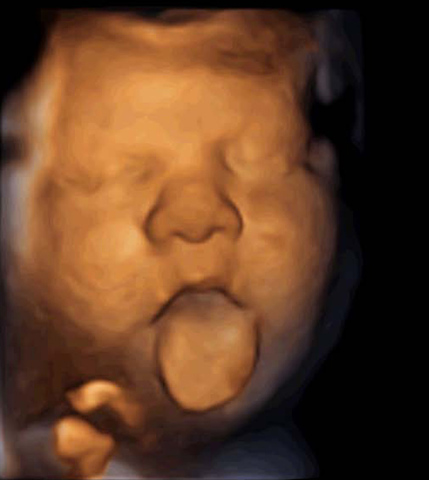

• 32 Semanas de Gestación

32 Semanas de Gestación

El feto orina al rededor de medio lito de orina diario, algunos órganos ya funcionan como la harán despúes del nacimiento como el estomago, intestino y riñones, otros aun no estan preparados como los pulmones y el higado solo en el 8vo mes se completa su crecimiento